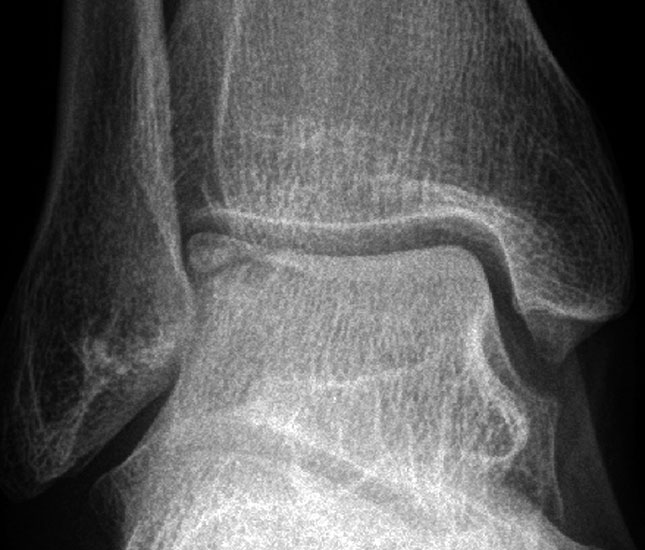

Laterale Läsionen entstehen meist durch ein akutes Trauma mit dorsalflektiertem und invertiertem Sprunggelenk, was zum Anschlag des Talus an der Fibula führt. Diese Läsionen sind meist vorderen Anteil der Talusrolle zu finden 7. Mediale Läsionen sind eher mit wiederholten Supinationtraumata verbunden oder treten aus ungeklärter Ursache auf. Insgesamt sind mediale Läsionen häufiger und meist im mittleren und hinteren Drittel des Talus zu finden 7. Laterale Läsionen sind von ihrer Konfiguration her eher flach und „waffelförmig“ (wafer-shaped) (Abb. 1), während sich mediale Läsionen eher tiefer und „tassenförmig“ (cup-shaped) darstellen (Abb. 2).

Röntgen

Die konventionell im Stehen durchgeführte Röntgenaufnahme des oberen Sprunggelenkes in zwei Ebenen (a.p. mit 20° Innenrotation und seitlich) steht am Anfang der bildgebenden Diagnostik. Die Röntgenaufnahme besitzt allerdings für die sichere Detektion einer Läsion, insbesondere bei geringgradigen oder kleinen Läsionen, eine geringe Sensitivität mit Raten nicht-diagnostizierter Läsionen von bis zu 41% 18.

Bei Fußdeformitäten oder Achsabweichungen sollten weitere Aufnahmen (z.B. Ganzbeinstehaufnahme, Rückfußaufnahme (Saltzman view), ganzer Fuß in zwei Ebenen im Stehen, angefertigt werden um evtl. ursächliche Pathologien besser beurteilen zu können. Posteromediale oder posterolaterale Defekte werden evtl. erst durch eine Spezialaufnahme mit 4mm Fersenerhöhung und Plantarflexion sichtbar 18. Anterolaterale Läsionen, welche häufig bei Akuttraumata anzutreffen sind, können besser in leichter Dorsalextension eingesehen werden 19.